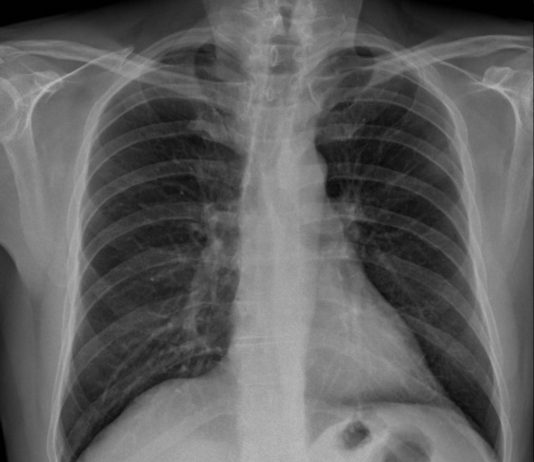

62-year-old male patient with fever, cough and asthenia for three days. No previous medical history. pO2 97%, C.RP 0.75.